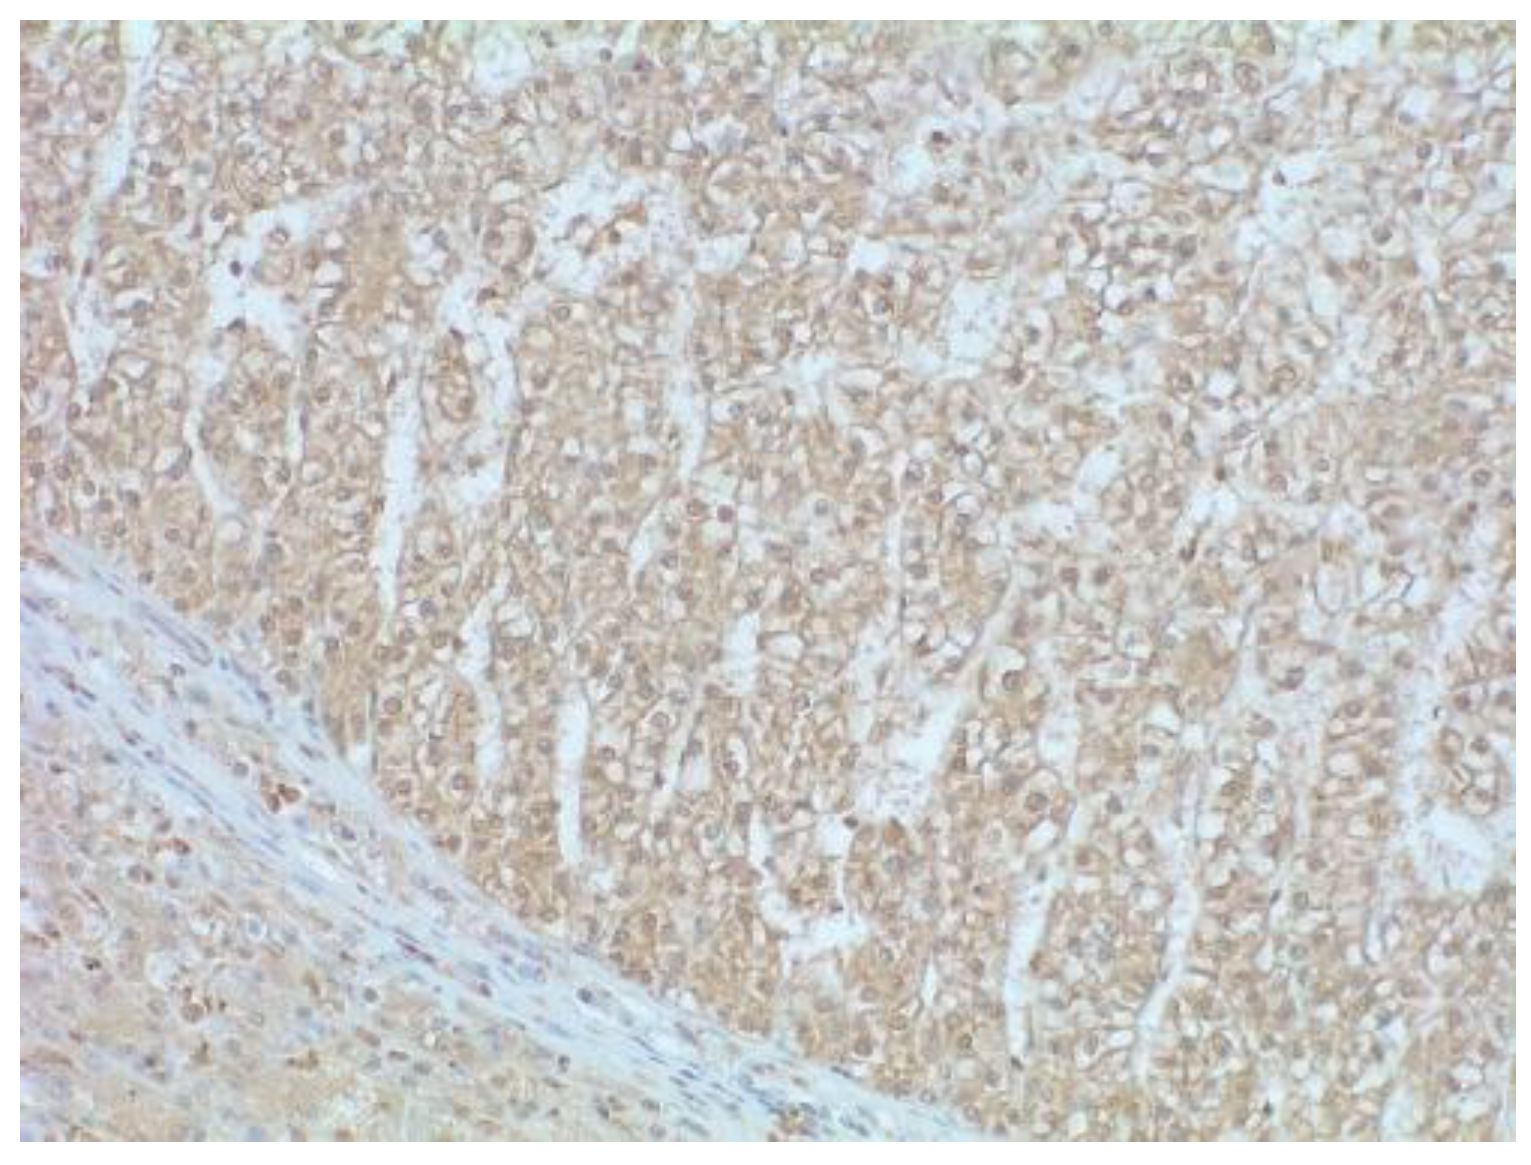

The application of histological grades identified an extreme variability in terms of grade when the method proposed by Martins-Filho and colleagues was applied [4], depending on whether the grade of architecture, nuclear or nucleolar morphology was assessed. The results are summarized in Table 2. PIVKA-II immunopositivity was observed in the cytoplasm. However, a weak positivity was present in the peritumoural liver tissue in all cases (Figure 1). Fifteen out of 22 cases (68.18%) were PIVKA-II positive while 7/22 were negative (31.82%).

Figure 1. HCC well differentiated (WHO grade) trabecular pattern positive for PIVKA-II. In the image a portion of peritumoural hepatic tissue (bottom left) with a weak cytoplasmic positivity for PIVKA-II is also represented. Peritumoural fibrous capsule is negative.200× magnification–Mayer’s hematoxylin counterstaining.